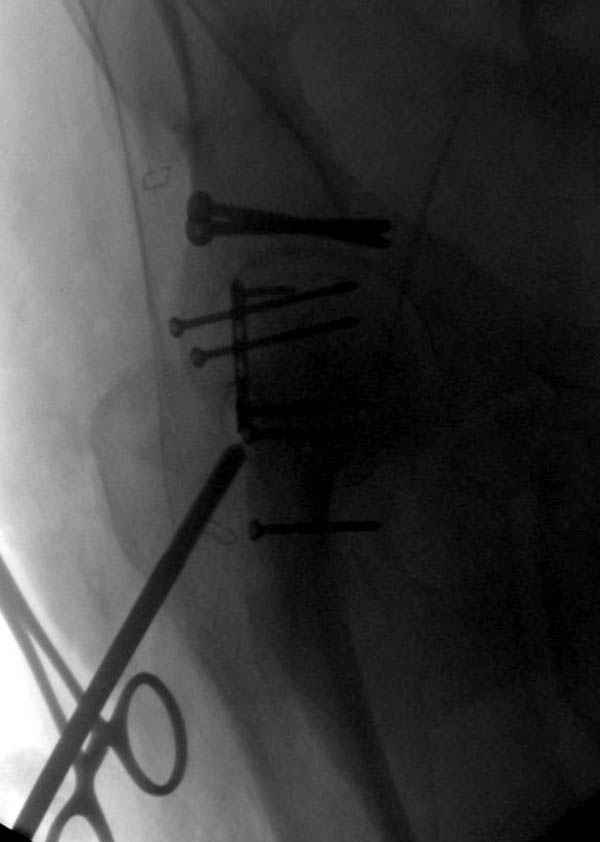

По возможности вышлите снимки, сканы таза до

реконструкции, интраоперационные.

По снимку создается впечатление о высоком поперечном переломе, задней колонны, стенки; почему не пользовались *magic screw*?

Положение больного на животе или на боку?

Не хотелось отклонятся от основной темы, поэтому здесь краткие ответы..

Латеральное положение облегчает проведение тракции через вертел, за 5 мм стержень за вертел (грузом через тракционное приспособление), на обычном рентгенопрозрачном операционном столе, а для положения на животе, наверное, Judet Table более приемлем, потому что там имеется латеральное тракционное устроиство.

Там множество обычных 2.7 мм шурупов, потом идет фиксация основными пластинами.

Снимки здесь....